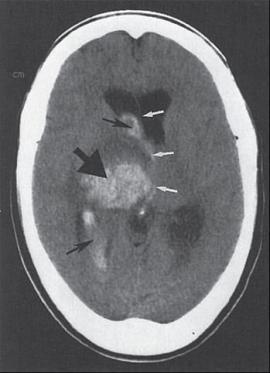

Fig.2 MRI scanning of Brain

To get a difference between the white matter and gray matter, MRI is used for tumors and aneurysms diagnosis purpose. M.R.I does not depend on the x-rays. MRI is more cost effective for x-ray imaging and C.T scanning. Especially for Functional Magnetic Resonance Imaging (FMRI), is used to observe the structure of the brain where the brain is particularly active during various types of cognitive tasks. By using this, we can advance the level of MRI through the Neurological status and the Neurological risk and get some good potential for understanding the brain organization